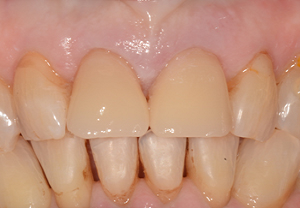

Cas 3 : Couronne toute céramique sur inlay-core céramisé et facette céramique sur deux incisives centrales chez un homme

La réalisation concomitante avec la même céramique usinée sur deux incisives centrales supérieures d’une couronne céramique sur dent dépulpée et d’une facette sur dent vivante permet d’optimiser le rendu esthétique du sourire